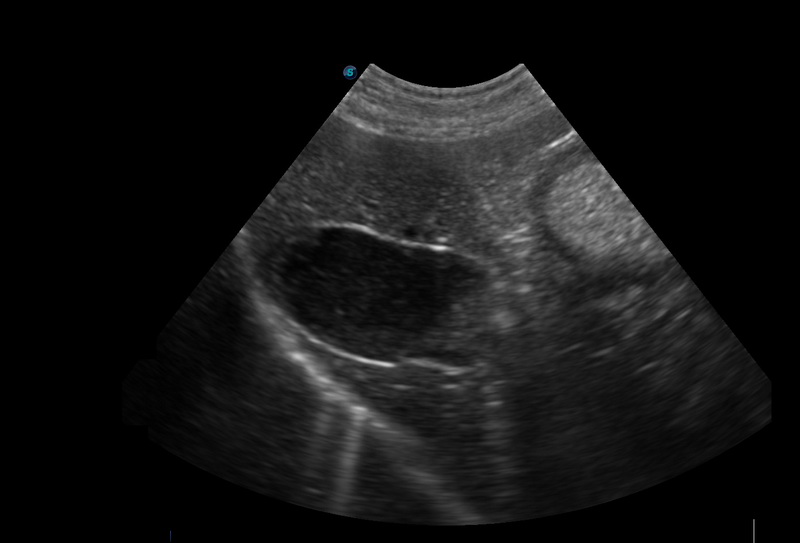

• 探頭,影像皆屬彩超等級處理配置

• 具備影像後處理功能